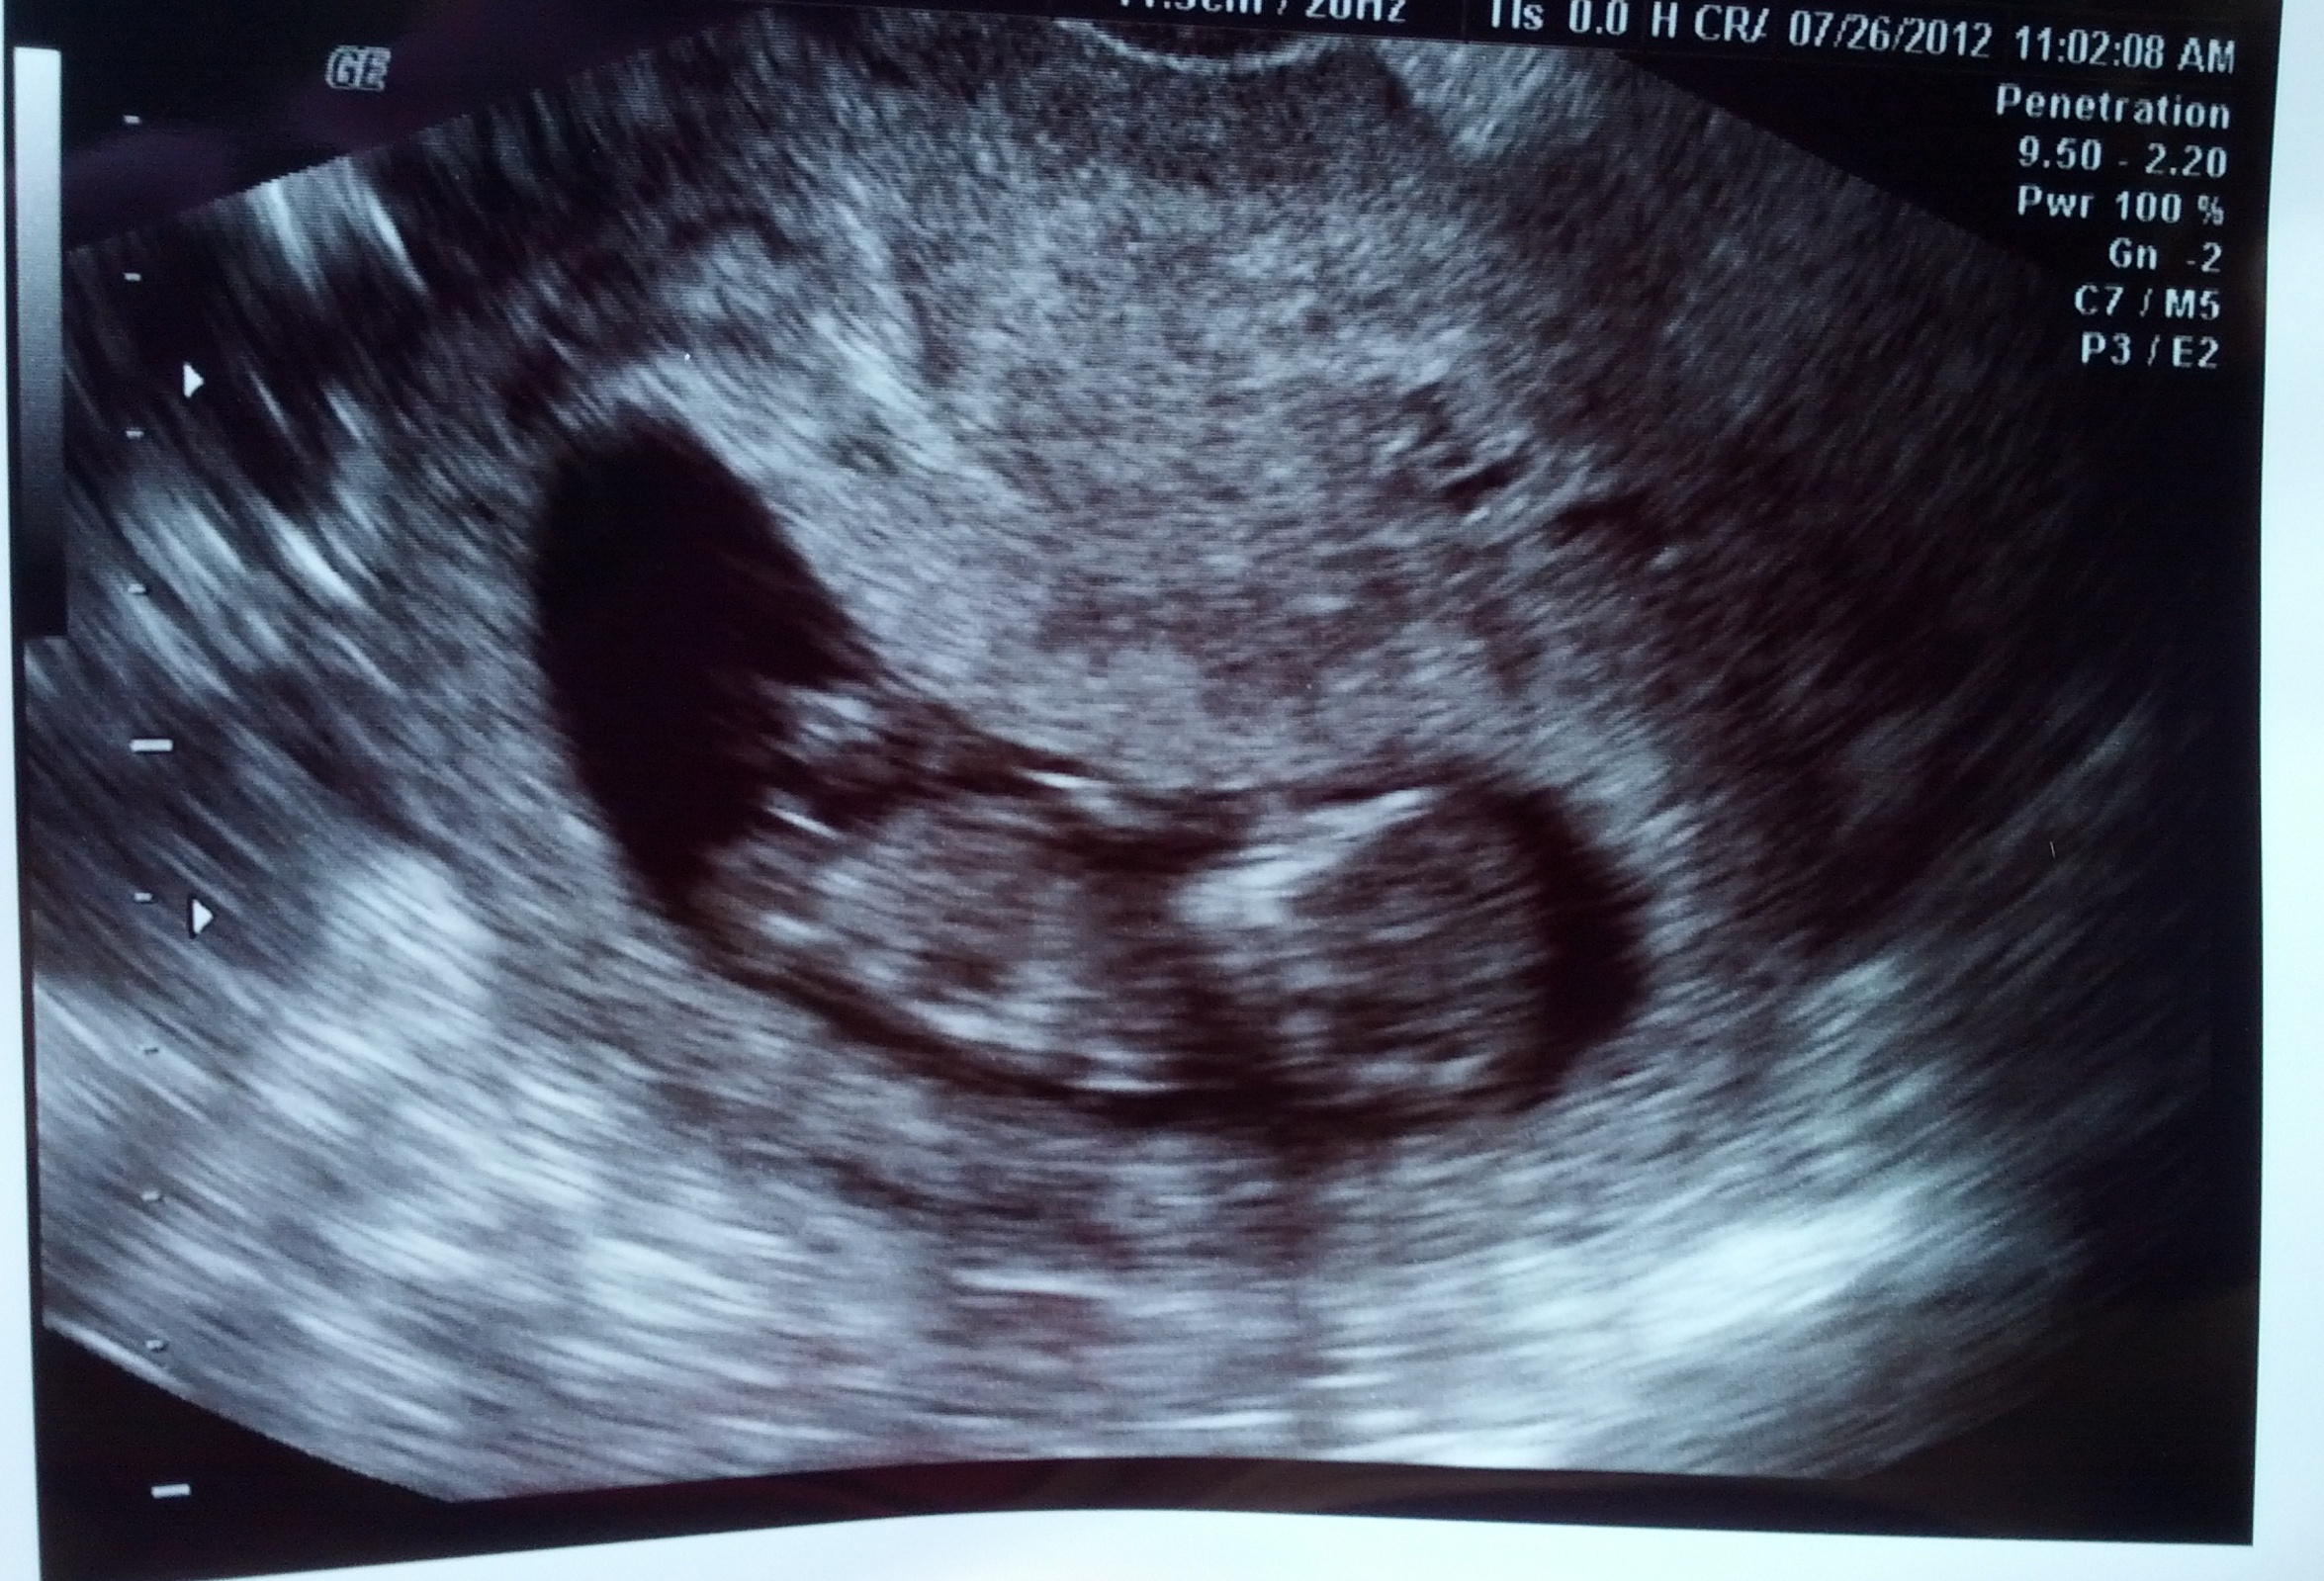

The tech told me the baby was not in profile view...but I've had a couple people tell me they think it is in profile. The nub is very visible, but I"m not sure if it's a reliable position to guess from? Please give me your honest opinions of what direction the baby is facing and whether a nub guess is possible...Thank you!!!

Attachment 4417